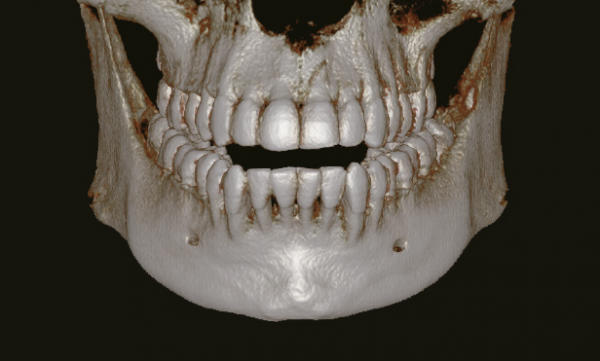

Одно сканирование – два изображения

Одно сканирование с Pax-i3D 10х8,5 (12X9)

позволяет получить не только CT,

но и панорамное изображение. Это означает, что пациенты, которым нужны оба исследования не

будут подвергаться дополнительному облучению. Кроме того, оба этих исследования можно просматривать в одной программе.

(Доступно на Ez3D-iV4.0)